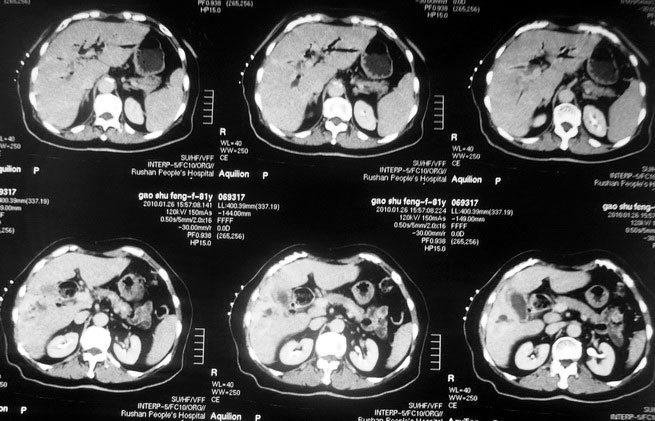

肝癌合并肝脓肿

女,80岁既往有胆系手术史。近2月出现食欲不振,近20天出现畏寒发热,体重约下降10kg,体温一般在38℃左右。血常规wbc正常,中性比例88%,cea 10.3,afp、ca199均正常。做过一次肝穿,抽出约3ml仿佛脓性液体。这是她的增强ct扫描,请大家帮帮忙。另外想问问肝脓肿和胆管细胞癌的ct表现有什么区别。谢谢了。

【湘江一滴】化脓性胆囊炎及胆管炎,肝内胆管积气、积液、扩张;胆囊壁增厚、强化;胆周积液。未见肝内占位征象。

【shuiyuan】化脓性胆囊炎及胆管炎,肝内胆管积气、积液、扩张;胆囊壁增厚、强化;胆周积液.

肝脓肿动脉期呈明显环形强化或蜂窝状强化,胆管细胞癌动脉期强化不明显,且伴肝内胆管扩张。

【zenxisengming 】肝内胆管扩张积气,胆囊比环形增厚,胆囊周围渗出,未见占位性病变,应该是胆道化脓性感染

【sunbin】肝内见多个气体密度影伴气液面,胆囊壁增厚,胆囊周围低密度环绕,未见强化,支持化脓性胆管炎、胆囊炎。

最近复查ct,做了第二次穿刺抽脓,顺便做了涂片病理活检,结果找到恶性肿瘤细胞,诊断肝癌合并肝脓肿。看来大家都走眼了啊。